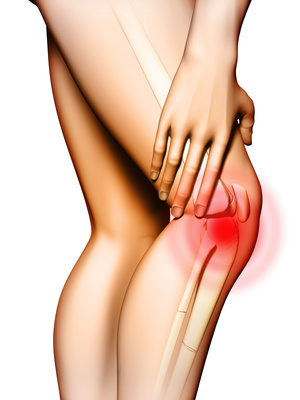

- zwyrodnienia stawów

- wspomaga terapię dolegliwości typowo sportowych (m.in. kolano skoczka, łokieć tenisisty)

- przyspiesza regenerację tkanek w zwyrodnieniach stawów

- poprawia funkcyjność zmienionych chorobowo stawów